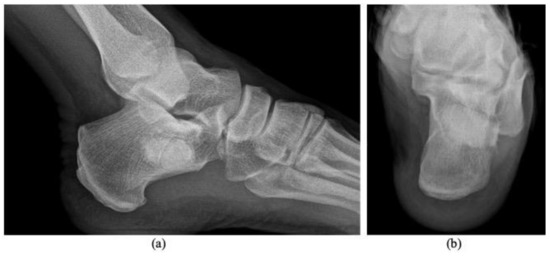

Symptomatic Intraosseous Lipoma of the Calcaneum

by Adyb Adrian Khal, Razvan Catalin Mihu, Calin Schiau, Bogdan Fetica, Gheorghe Tomoaia and Manuel Vergillos Luna

Diagnostics 2021, 11(12), 2243; https://doi.org/10.3390/diagnostics11122243 - 30 Nov 2021

Intraosseous lipomas are rare bone lesions that can affect any part of the skeleton. In the calcaneum, they are, generally, asymptomatic, but in some cases, patients may complain of pain, swelling or tenderness. Well-conducted radiography and MRI examinations can lead to an accurate [...] Read more.

Intraosseous lipomas are rare bone lesions that can affect any part of the skeleton. In the calcaneum, they are, generally, asymptomatic, but in some cases, patients may complain of pain, swelling or tenderness. Well-conducted radiography and MRI examinations can lead to an accurate diagnosis. In most cases, patients could benefit from conservative means of treatment, but in long-lasting symptomatic cases, surgical treatment may be a good option. The purpose of this article is to increase clinicians’ awareness of this lesion as a possible cause of heel pain and to describe a case of a symptomatic intraosseous lipoma of the calcaneum who underwent curettage and bone cement filling after failure of conservative treatment. Full article